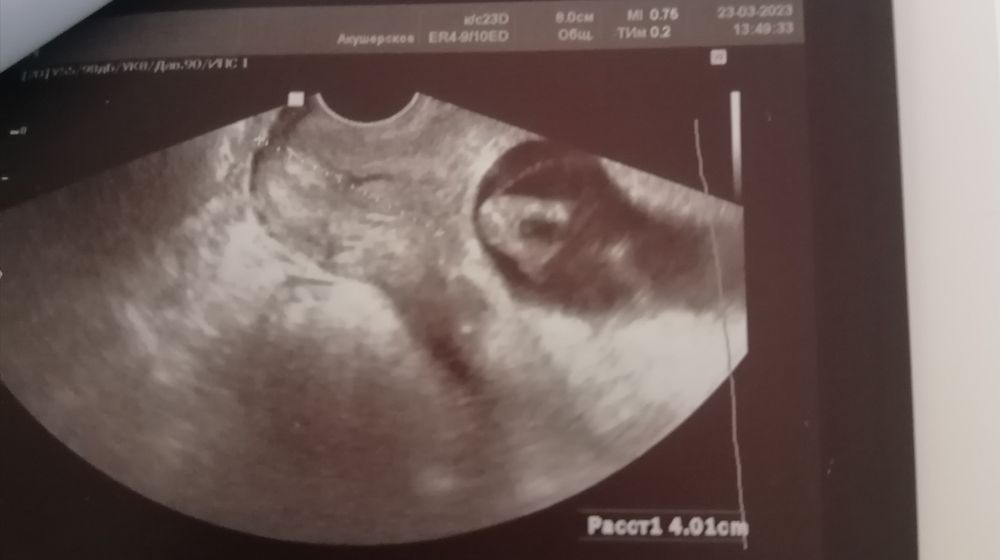

Девочки, кто, может разбирается в УЗИ, как думаете мальчик или девочка?

На фото вид снизу попа, ножки и, наверное, большой писюн между ног. Но гинеколог сказала что рано ещё для пола и у них у всех в 12 недель ещё "шишка".

Это пуповина. На таком сроке смотрят в другом ракурсе, по наклону полового бугорка

Врач права , у меня на узи в 11,4 такое же было между ног.. но в итоге девочка🙈👼🏼 советую сдать кровь и не гадать по узи, малыши часто прячут свои гендерные признаки)

Это может быть пуповина

Вот моя дочь тоже в таком же ракурсе, только чуть подальше. Между ног оказалась пуповина, хотя узист сказал, что 90% мальчик. И только в 20 недель мой мальчик превратился в девочку 😄

Не шишка, в половой бугорок и на этом сроке он одинаковый у всех